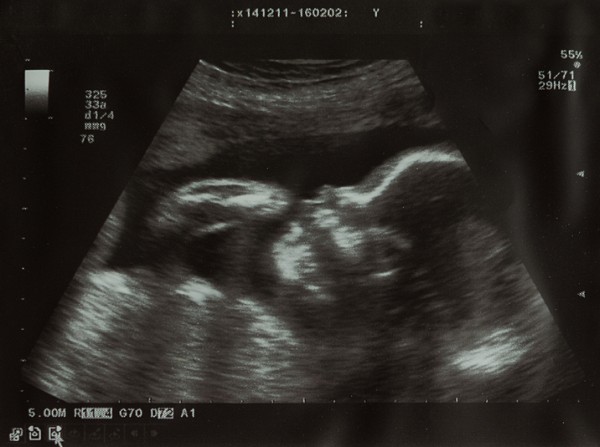

УЗИ НА 24 НЕДЕЛЕ БЕРЕМЕННОСТИ

Ультразвуковое исследование на двадцать четвертой неделе беременности

Ультразвуковое исследование на двадцать четвертой неделе беременности обычно проводится по желанию женщины. Оно позволяет оценить развитие плода и выявить возможные внутриутробные патологии.

Во время УЗИ специалист анализирует множество показателей: рост и вес плода, сердечный ритм, состояние внутренних органов и головного мозга, уровень физической активности, объем околоплодных вод, а также состояние плаценты и пуповины. Врач также проверяет наличие аномалий в развитии.

Кроме ультразвукового исследования, женщине рекомендуется регулярно контролировать артериальное давление и следить за изменениями массы тела.